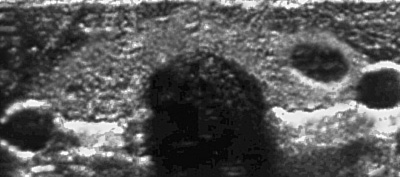

A 43-year-old previously healthy woman has a routine medical checkup. Her physician palpates a firm nodule in her left neck region. An ultrasound scan reveals the following: